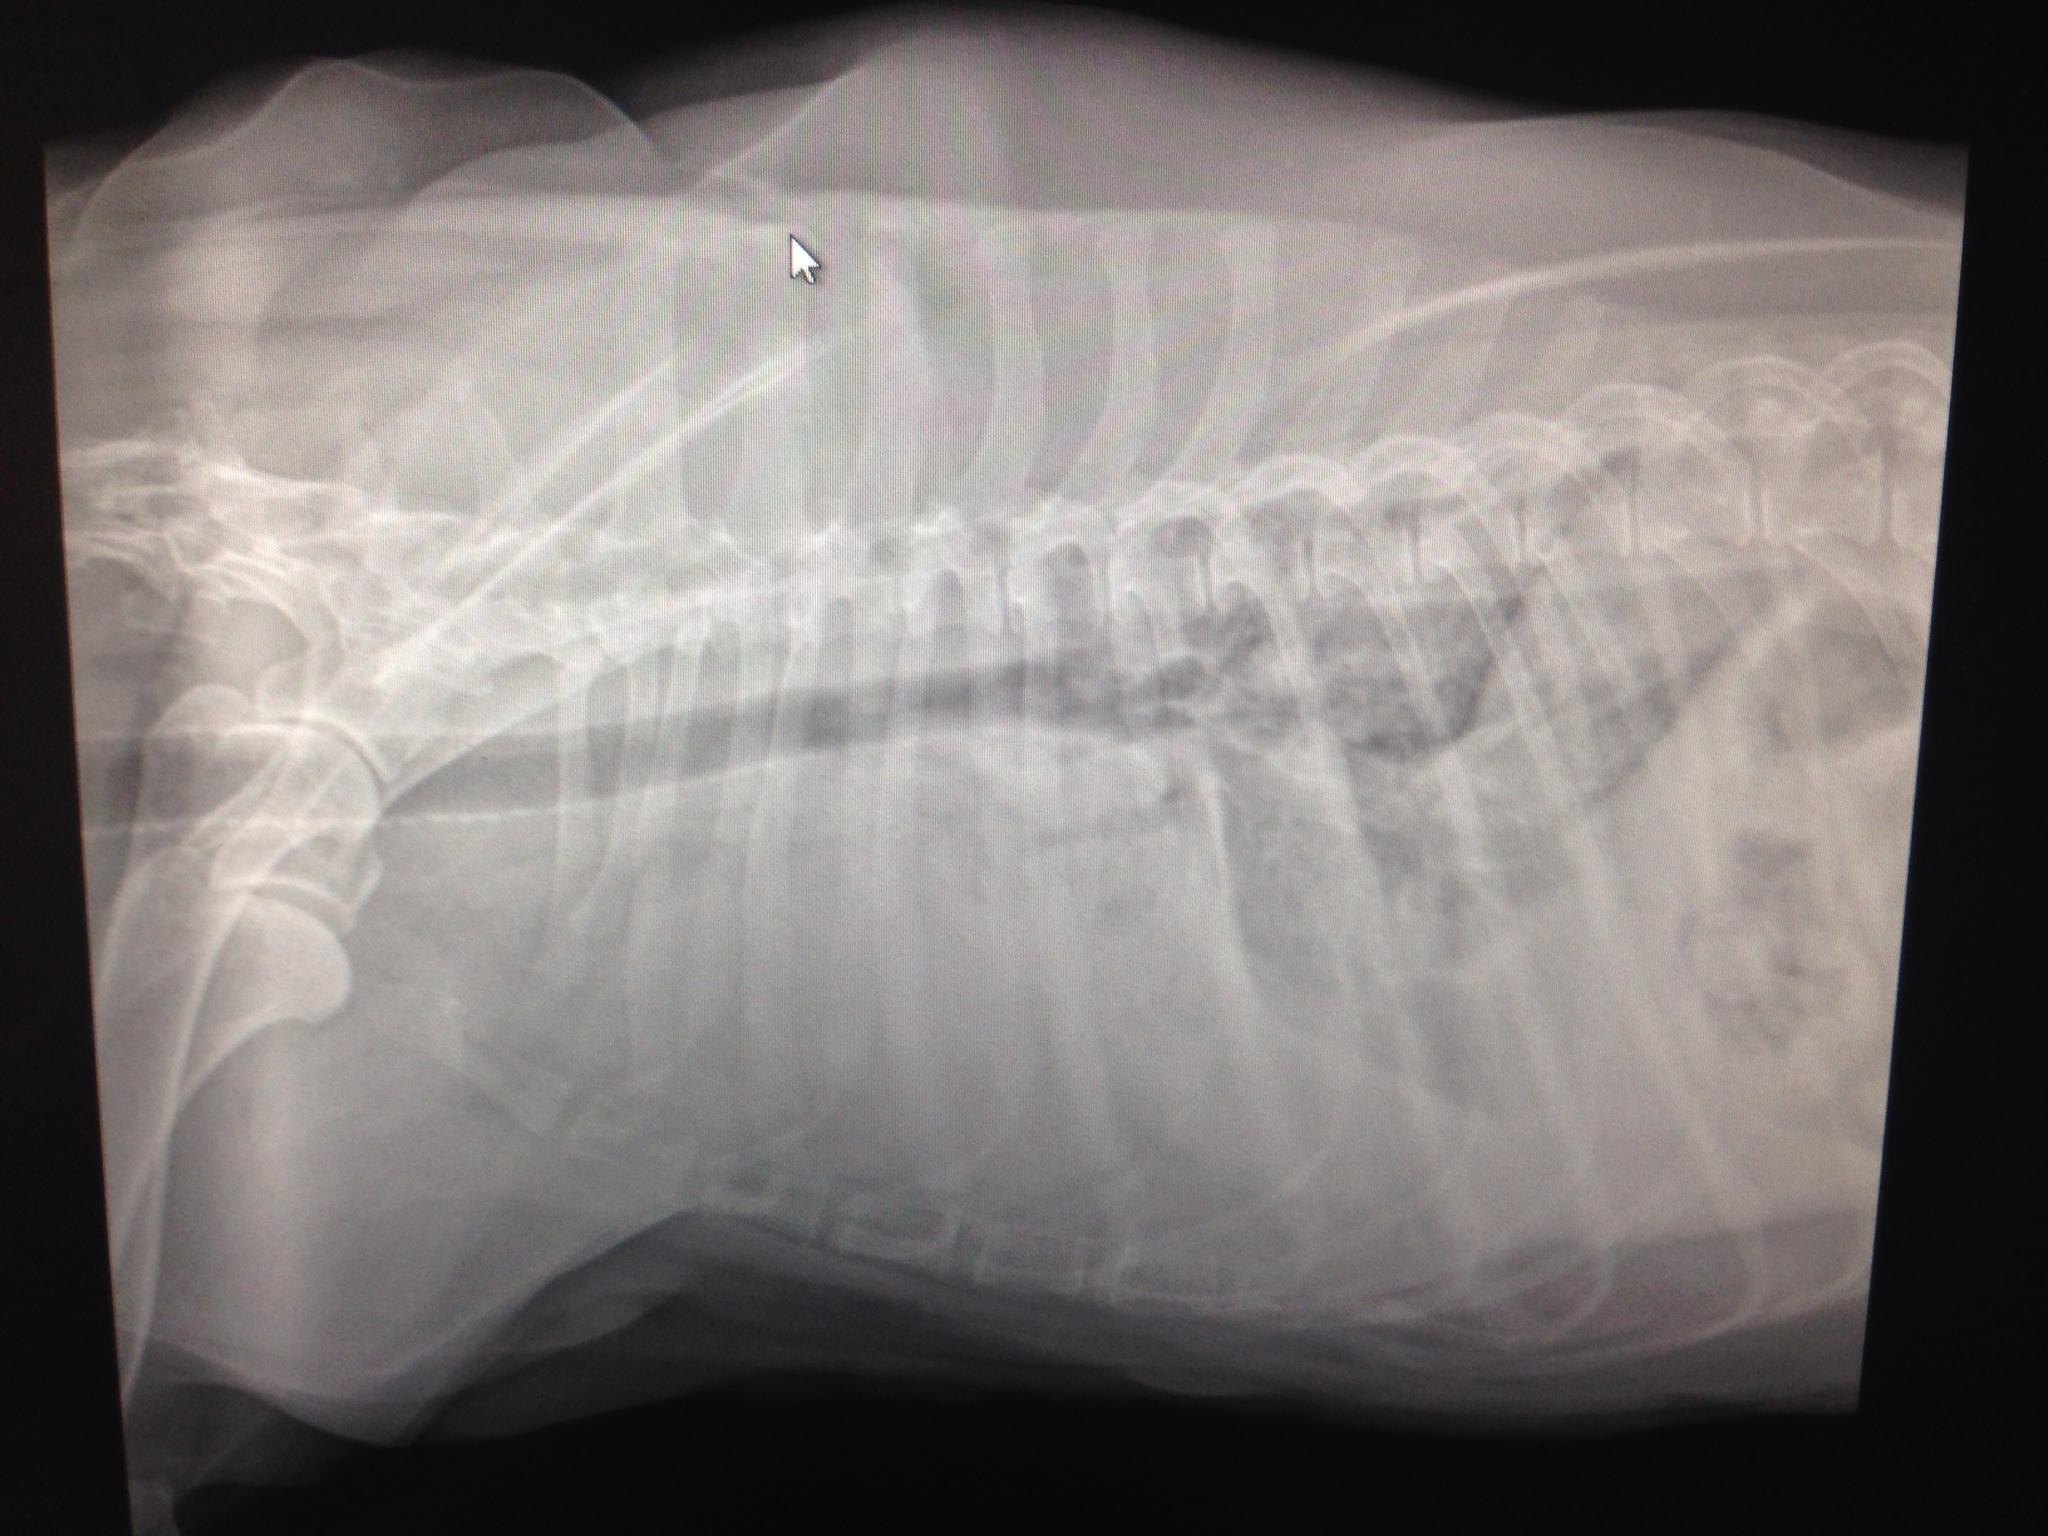

A 9-year-old SF Golden retriever was presented for evaluation of coughing and lethargy. On survey radiographs a left cranial lung mass was evident.

Left cranial lung mass was noted which was significantly hypoechoic and irregular with some cavitation. FNAs were performed without complication. Peripheral air entrapment was noted, which is indicative of lung origin. This may be resectable. CT evaluation would be ideal.